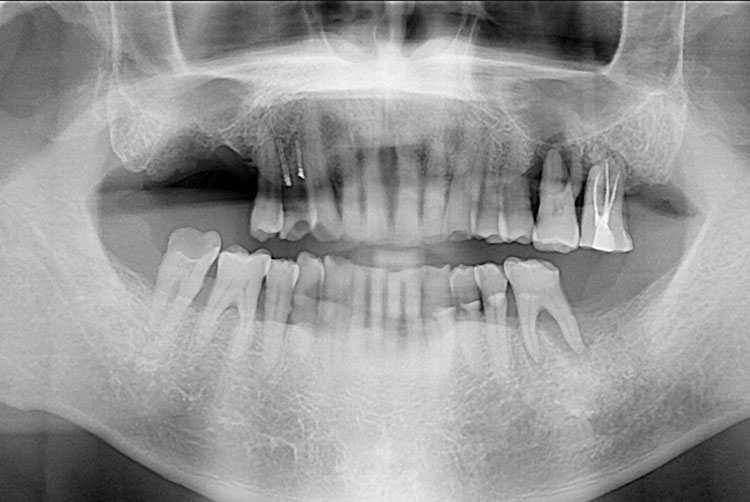

[임플란트] 임플란트

치료전 : 2017-10-20